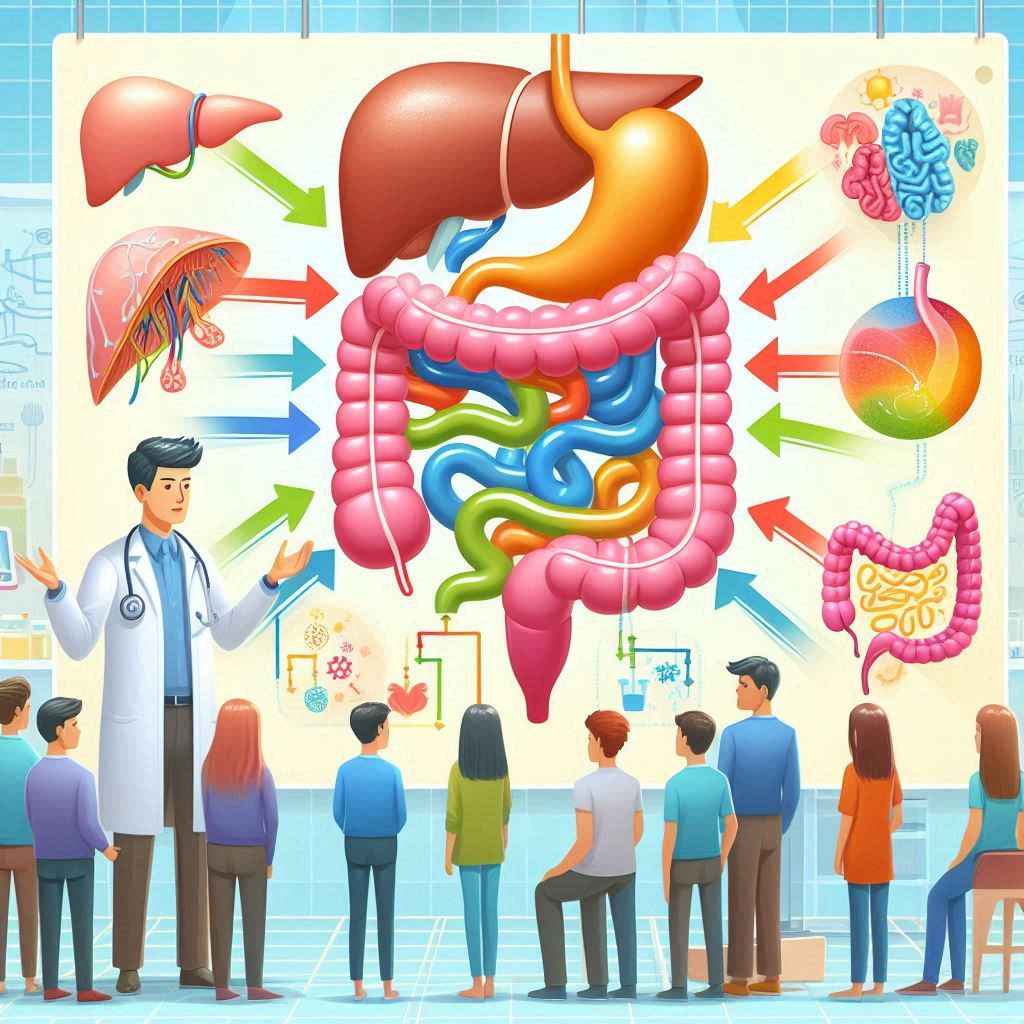

Read MoreUna Terapia Innovadora para el Dolor Crónico, la Inflamación y el Sueño El nervio vago es uno de los principales nervios del sistema nervioso autónomo, desempeñando un papel crucial en la regulación de múltiples funciones corporales. Su influencia abarca desde la modulación del dolor hasta la regulación del sueño y la inflamación. La estimulación auricular eléctrica del nervio vago (taVNS, por sus siglas en inglés) es...